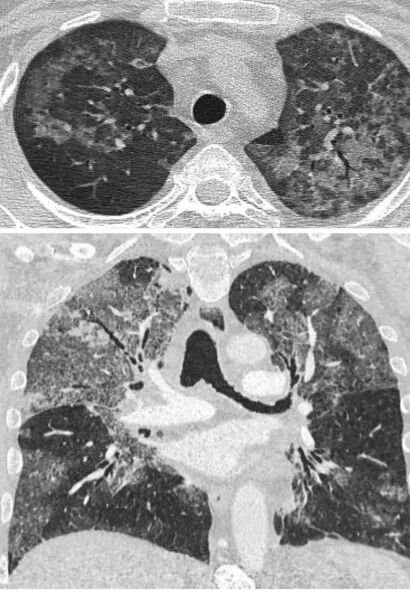

耶氏肺孢子菌肺炎胸部CT特征性改变

非HIV患者PJP的胸部CT特点主要为[27, 28]:①广泛的大片磨玻璃影,上肺近肺门为主,外周病变较少;②黑边征,胸膜下无病变,无磨玻璃影,这是其与非特异性间质性肺炎(NSIP)之间的鉴别要点;③铺路石征:由于肺泡腔中气体含量轻微减少,其气腔被液体、细胞或其他物质填充,肺实质密度呈磨玻璃影外观,小叶间隔和小叶内间隔呈网格状增厚,提示病情较重;④多发囊性变或空洞:具体机制尚不清楚。

PJP在影像学方面有时很难与CMV感染相鉴别,CMV感染有一个很重要的特点,即在HRCT上可见多发小叶中心结节。北京大学第一医院的一项回顾性队列研究纳入70例非HIV PJP患者,其中54.3%合并CMV感染,与使用皮质类固醇相比,接受糖皮质激素和免疫抑制剂的患者肺部CMV感染明显更常见;合并CMV感染也与重度呼吸困难有显著相关性,影像学可见小叶中心结节,BALF中高CMV DNA负荷量与死亡率呈正相关[29]此外,我们也不能满足于单纯PJP诊断,也要警惕PJP合并曲霉等其他机会性感染的发生。